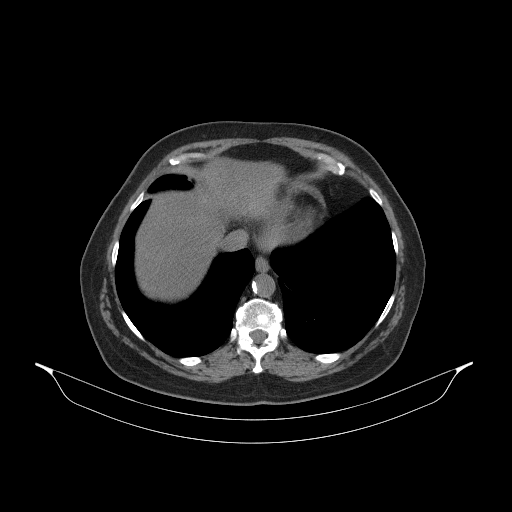

Image Grid

4Γ—3 grid: Rows show different image types (Original NATIVE, Reconstructed NATIVE, Original VENOUS, Generated VENOUS), Columns show windowing techniques (No Window, Lung Window, Mediastinum Window)

Generated VENOUS CT scan (A→B translation)

Full window (WL 1023.5, WW 4095 β†’ Low βˆ’1024, High +3071)